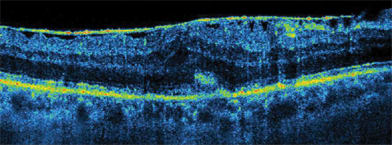

A key feature of the SOCT Copernicus is its ability to segment the layers of the retina. "It is able to segment the internal limiting membrane, the retinal nerve fiber layer, the junction between the inner segment (IS) and outer segment (OS) of the photoreceptors, and the top and bottom of the retinal pigment epithelium (RPE)," Dr. Sharma says. "This allows tracking of changes in thickness of each of these layers without having to manually measure their thickness."

Carlin explains, "Our system's algorithms allow for excellent visualization of multiple retinal layers, including the external limiting membrane. Many manufacturers have systems that have 5 to 6 μm resolution, but the resulting images still may not be as clear. The Copernicus definitely lets physicians see things that other systems do not."

2. Tomogram image processing software. Algorithms used by the Copernicus to process images are the product of years of advancing science by individuals on the forefront of such technology. While an expanded discussion of the algorithms is beyond the scope of this article, 1 example of the benefits of the algorithms is the clearly observable IS/OS junction that can be seen in detail with the Copernicus.